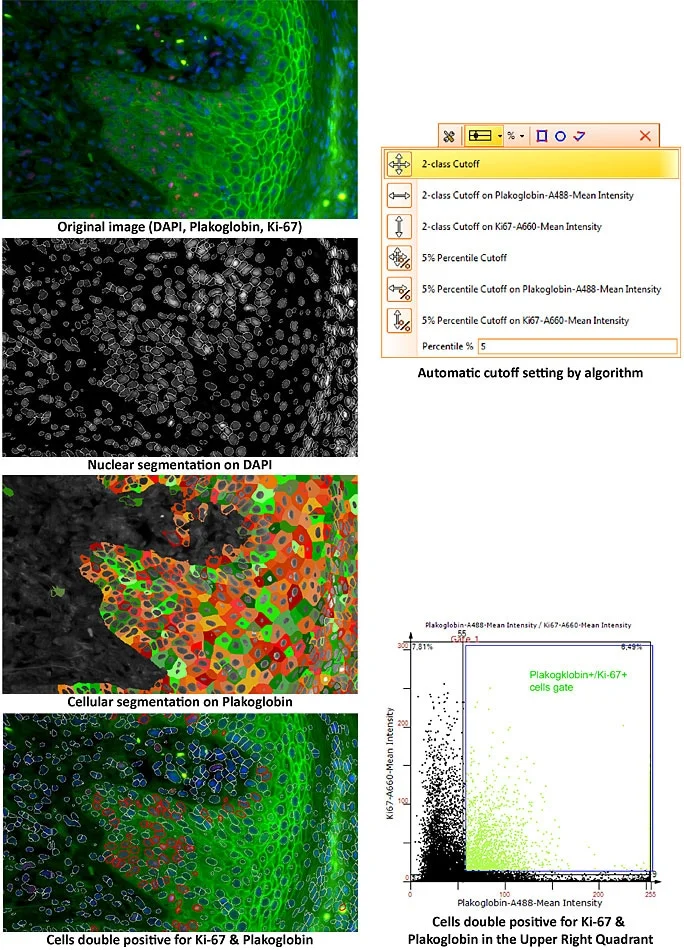

Revolutionizing Tissue Analysis: Image-Based Cytometry

Image-based cytometry is transforming tissue analysis by combining microscopy with flow cytometry features. It enables rapid, automated characterization of cells in their native environment, advancing pathology, oncology, and precision medicine with AI integration.

How to Carry Out Complex Characterization of the Tissue Microenvironment

Characterizing the tissue microenvironment reveals how cells and structures interact in health and disease. This blog highlights its role in cancer research and how TissueGnostics solutions enable advanced imaging and quantitative analysis.